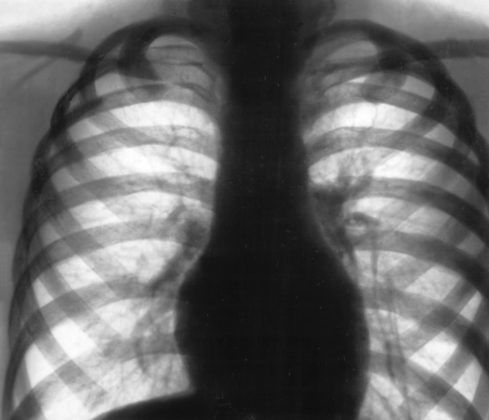

Характерна картина на рентгенівських знімках — це посилення і деформація легеневого малюнка. А також з’являються тіні, які вказують на ділянки ушкодження нормальних тканин. При запущеній формі фіброзу вся поверхня органу спотворена:

- малюнок нагадує бджолині стільники;

- порушується капілярна мережа;

- з’являються анастомози.

Рентген дифузного пневмофіброз

Бронхографія при дифузному фіброзі не вкаже на видимі зміни, а при локальному будуть з’являтися типові розширення.